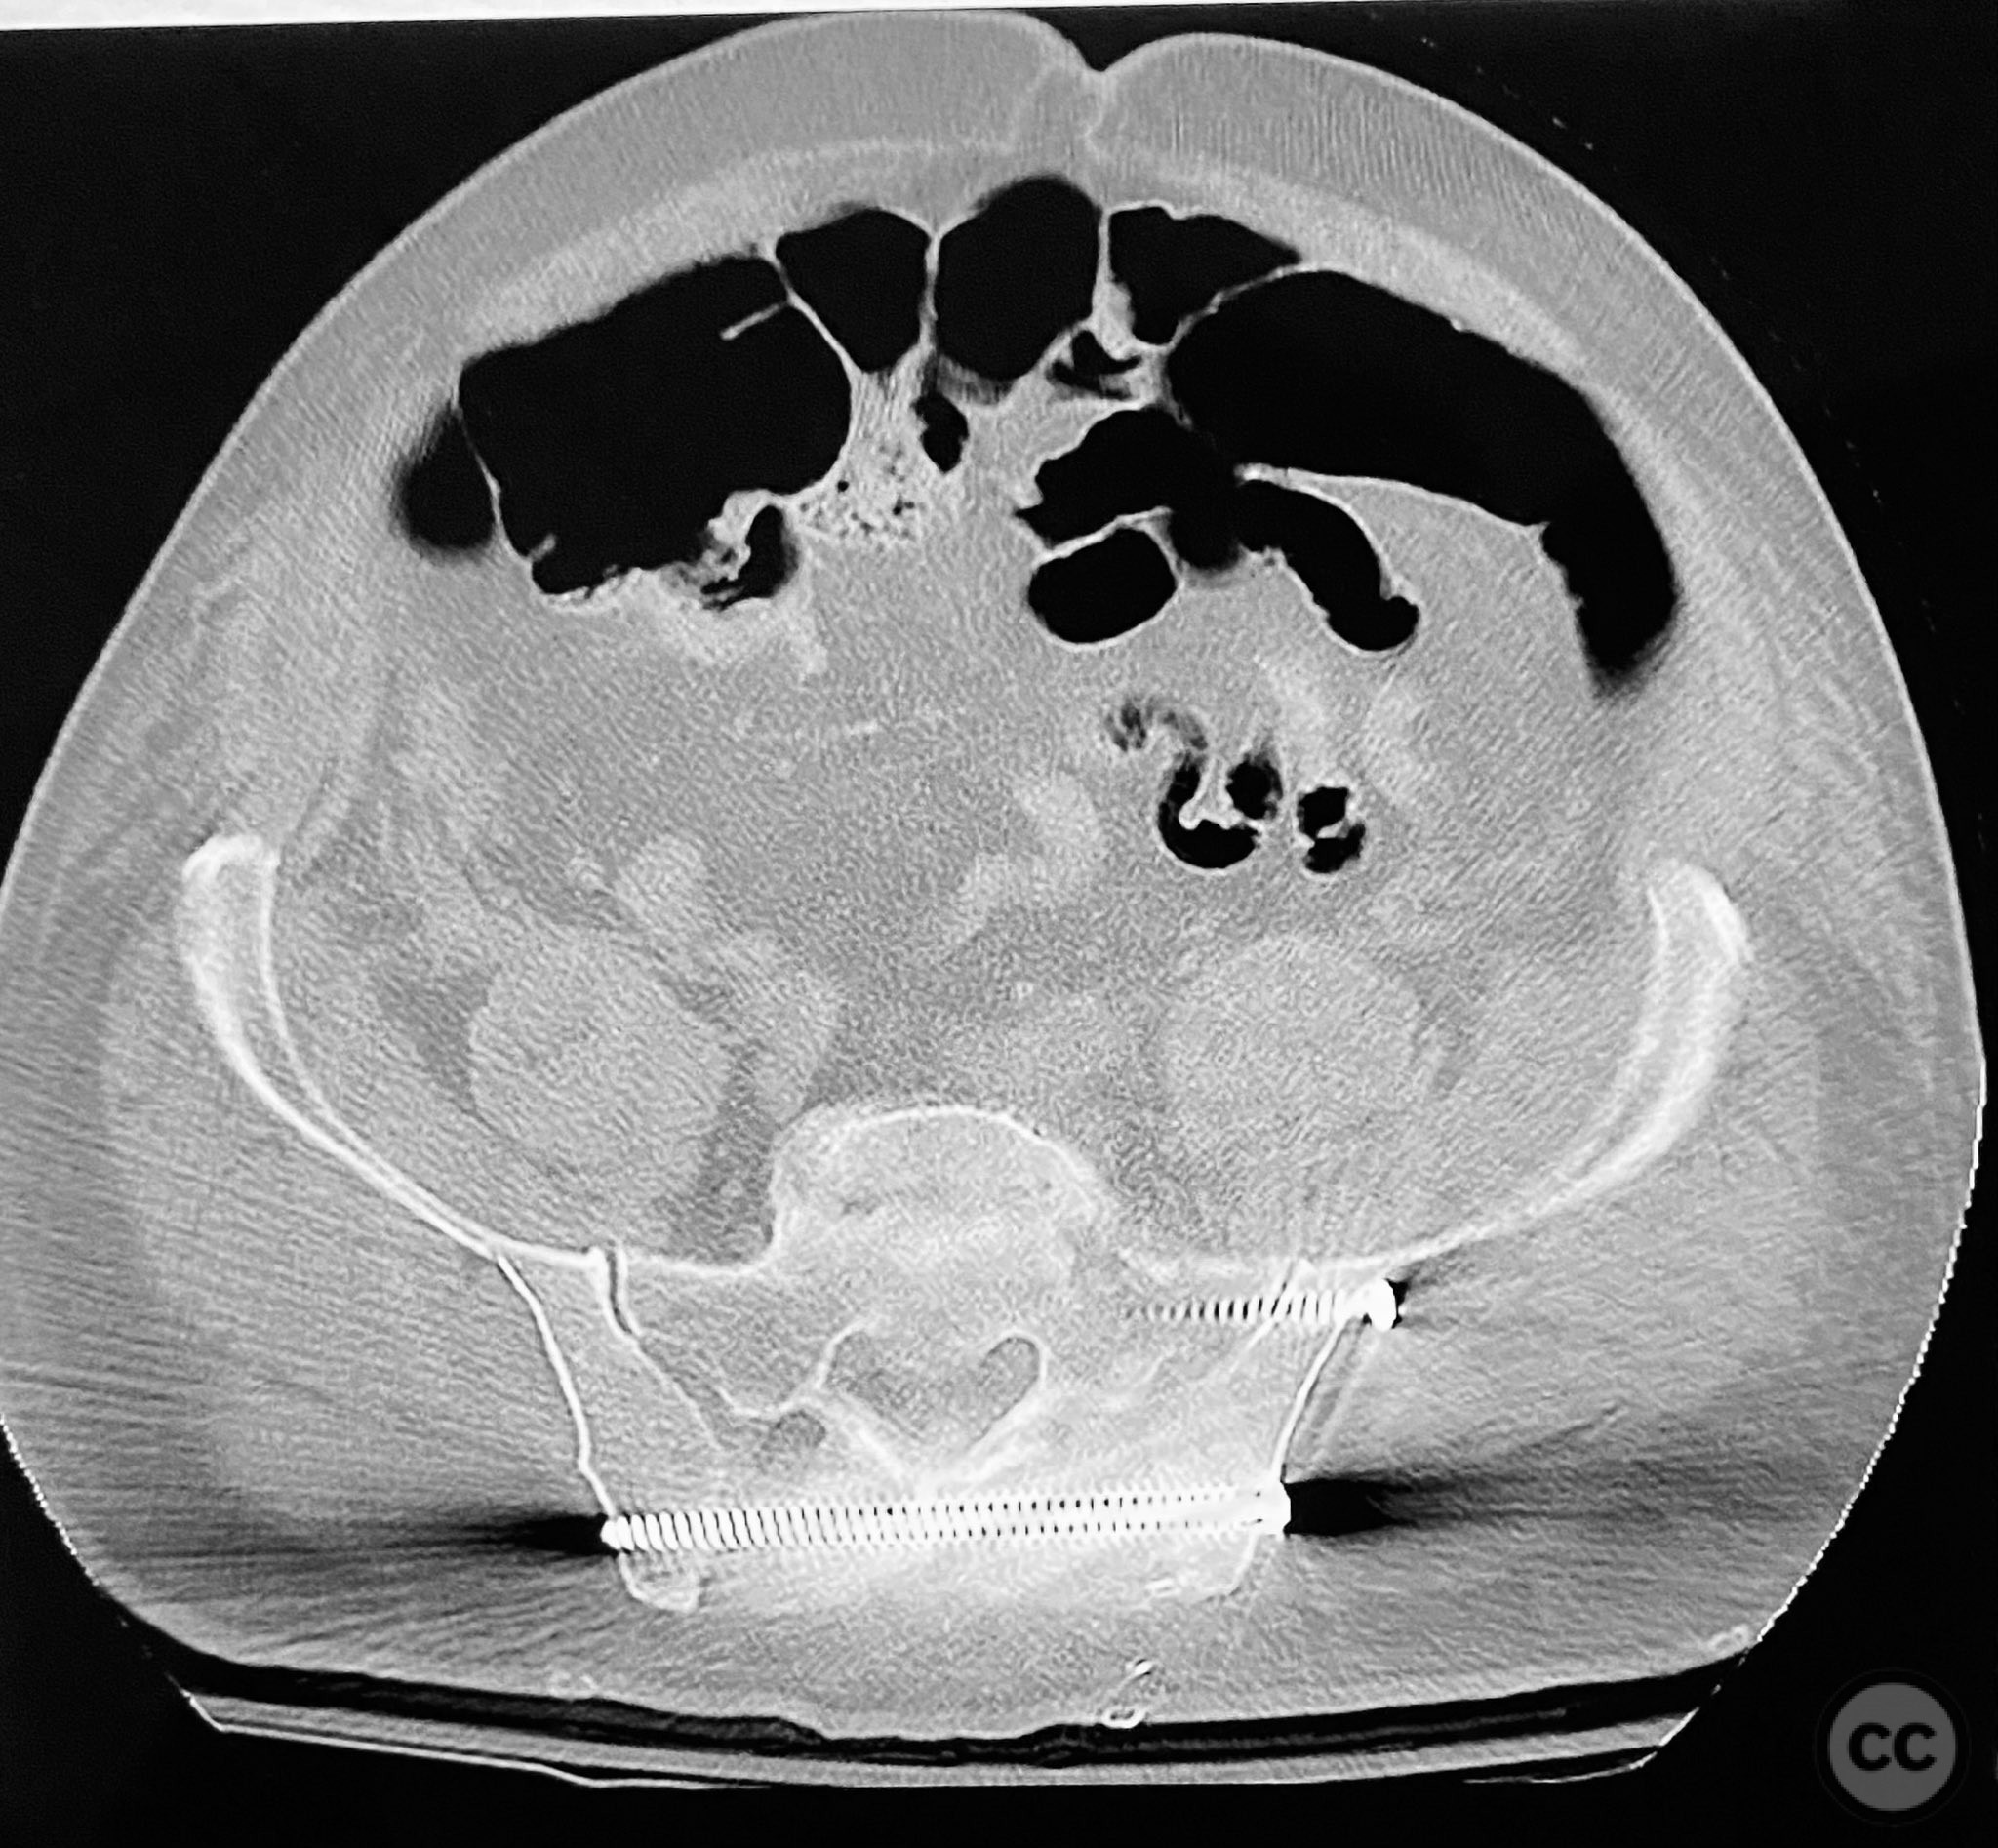

Clinical and radiological findings:  Middle-aged male with a high-energy pelvic ring injury, presenting with significant pain and mechanical instability. Initial radiographs demonstrated comminution and displacement of the posterior pelvic ring, including sacral fractures and disruption of the anterior ring at the pubic symphysis and rami. Application of a circumferential pelvic sheet provided partial reduction and improved comfort. No neurovascular deficits were noted. CT imaging confirmed a comminuted sacral fracture (AO/OTA 61-C1.3), with bilateral pubic rami fractures and symphyseal diastasis. The posterior elements demonstrated both vertical and rotational instability.

The staged approach allowed direct assessment and refinement of posterior reduction using dorsal cortical landmarks, which was critical given the comminution and displacement pattern. The absence of long cannulated screws limited optimal iliosacral screw placement; screws were contained within the osseous fixation pathway but not ideally positioned for maximal safety or precision by contemporary standards. Anterior ring stabilization was performed after confirming satisfactory posterior reduction on postoperative CT. The sequence addressed both vertical and rotational instability, but implant limitations may have increased risk for suboptimal fixation or neurovascular compromise. In current practice, advanced imaging, navigation, and longer cannulated screws would be utilized to optimize screw trajectory and safety.